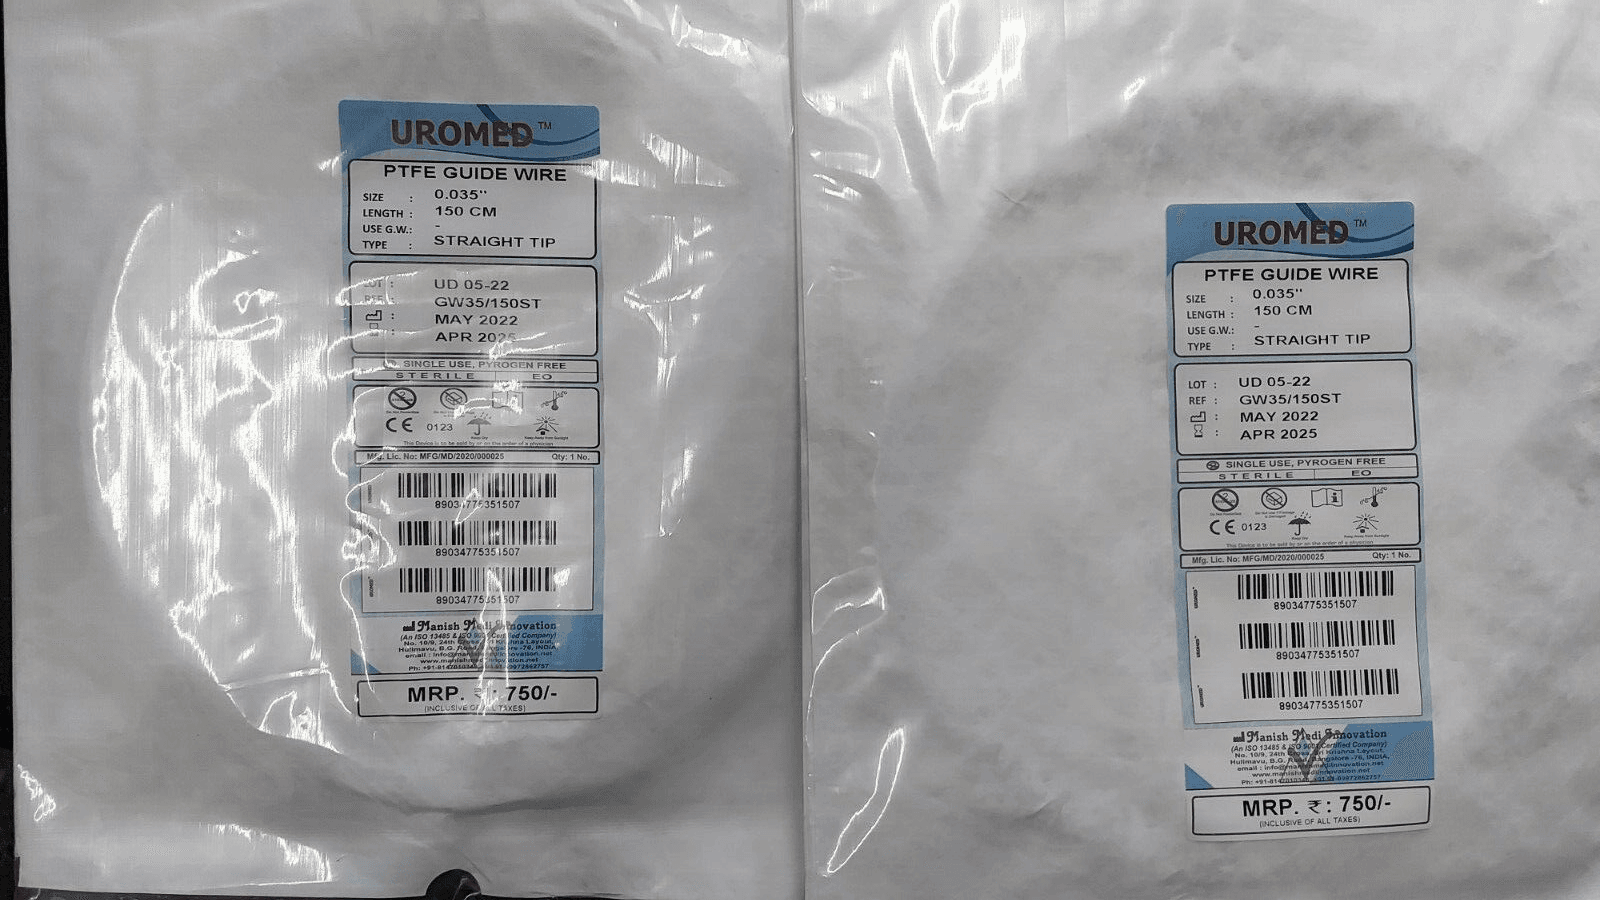

PTFE Guide Wire Set of 10 Urology Size 0.035 Length 150cm Straight

PTFE Guide Wire Set of 10 Urology Size 0.035 Length 150cm Straight

Guide wire with and without PTFE coating

- This wire is made by Galvanized Stainless Steel, and having fixed core. UROMED guide wire has excellent flexibility.

- Better push ability for increased placement control.

- Low of coefficient of friction for smooth advancement.

- Size: 0.035”

- Lengths: 150cm

Images are for illustration only. Company may change item design and packaging from time to time. We will ship latest stock available.